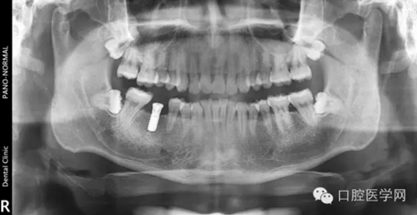

第二種種植體是 NobelReplace系統(tǒng)

X光片顯示為: